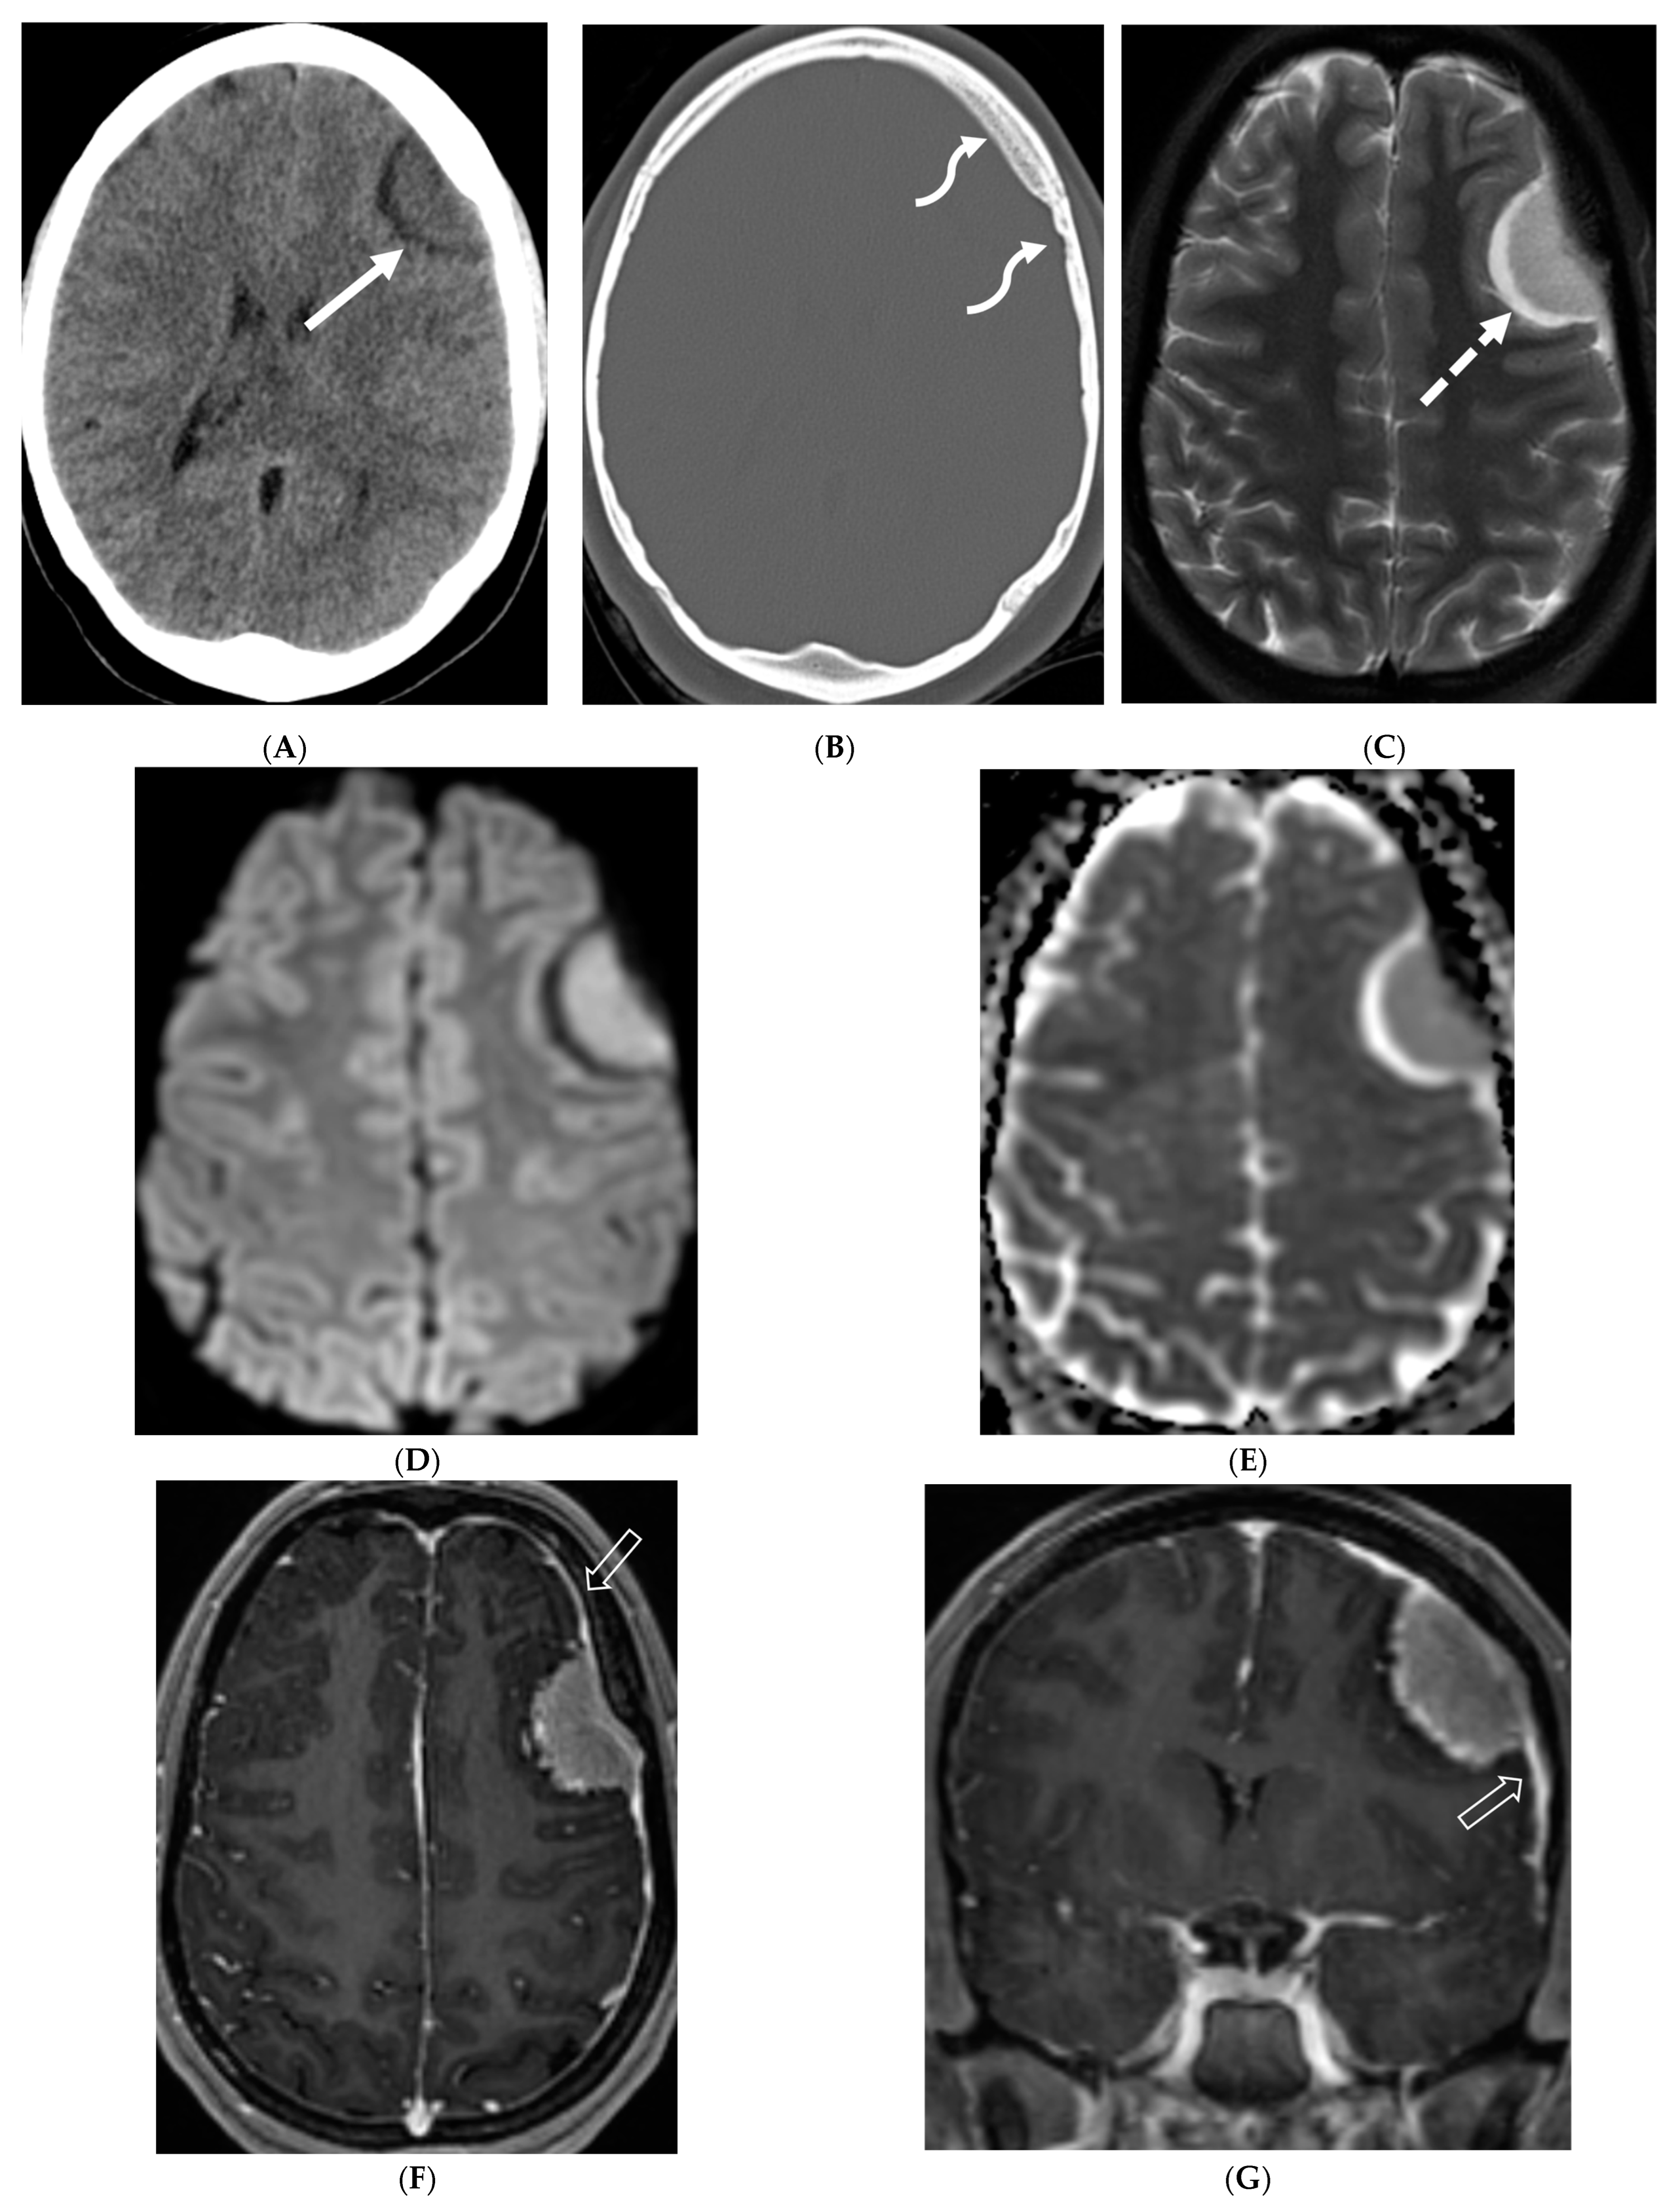

4.4. Systemic Meningeal Metastases (SMM)

Meningeal metastases from an extracranial primary tumor is a diagnosis with a grave prognosis, reducing the survival to less than 3 months if left untreated. Early and accurate diagnosis is essential for improving patient outcomes [84]. Leukemias and neuroblastoma are the most common primary malignancies in the pediatric population [85,86]. Leukemia is the only one which merits prophylactic treatment to avoid SMM.

The typical MRI presentation of SMM involves serpentine, nodular, or plaque-like enhancement in sulcal spaces, basal cisterns and along the cauda equina nerve roots [87,88]. Notably, SMM enhancement on post contrast [PC]-T1 images is superior to the PC-FLAIR in contrast to that seen in infectious meningitis [84]. However, in case of a non-enhancing primary tumor, FLAIR and DWI are important sequences to look for SMM. Hydrocephalus and subependymal deposits are other common features found in kids with SMM (Figure 15, Figure 16 and Figure 17). Positive cytology on CSF analysis, especially with leukemia, is important [89].

Figure 15.

Axial DWI (A), axial ADC (B), axial T1 FS post contrast (C) and Fluorodeoxyglucose Positron Emission Tomography (FDG–PET) scan (D): 13-year-old male with bilateral leg pains, headache, fever and weight loss: Blood tests and CT scan were concerning for Burkitt’s lymphoma. There is heterogeneous calvarial bone marrow signal with restricted diffusion (arrows) and patchy enhancement (curved arrows). Diffuse thickening and enhancement of pachymeninges in the supratentorial compartment is noted (dashed arrows). Findings are most consistent with lymphomatous involvement. Multifocal diffuse/heterogeneous pattern of FDG uptake within the axial and appendicular skeleton and the calvarium (open arrows). Intense FDG avid uptake is seen in the presacral mass (star).

Figure 16.

16-year-old female with 4 months history of globus sensation and recent botox injection of lower esophageal junction. Headache and vomiting for past week: Esophagogram (A), Axial T2 orbits (B), axial FLAIR (C) and post contrast T1 (D,E): Narrowing of the Gastroesophageal (GE) junction with beaked configuration and mild distention of the lower esophagus likely from early achalasia (black arrow). There is bilateral papilledema indicating raised ICP (dashed arrows) and sulcal hyperintensity (curved black arrows). Diffuse LME in the supra-and-infratentorial regions and along optic sheaths raising the concern for leptomeningeal carcinomatosis (white arrows). Pathology: Gastric adenocarcinoma metastasis.

Figure 17.

Axial T2 FS (A), axial Susceptibility weighted imaging (SWI) (B), axial DWI (C), post contrast sagittal and axial T1 post contrast (D,E): 19-year-old female with history of stage IV neuroblastoma, left paraspinal primary ganglioneuroblastoma, treated with chemotherapy, radiation and bone marrow transplant presents with headache. There are extensive hemorrhagic leptomeningeal masses, both supra and infratentorial region (arrows). The lesions also demonstrate restricted diffusion which could be secondary to internal hemorrhage or high cellularity of the tumor(curved arrows). The larger masses invade the cortex of both cerebral hemispheres, with surrounding vasogenic edema (black arrow). Avid enhancement of the lesions is seen along with overlying dura (dashed arrows). Features are in keeping with extensive leptomeningeal metastatic neuroblastoma.